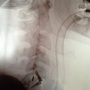

CANBERRA - Il fatto è accaduto venerdì 11 gennaio, ma la notizia è trapelata soltanto nelle ultime ore attraverso il portale di 20 Minuten online. Marco Grassi, ex giocatore della nazionale svizzera ed ex presidente dell'FC Chiasso, è rimasto vittima di un infortunio in Australia, che ha avuto come conseguenza la frattura della quinta e della sesta vertebra.

Trasportato all'ospedale, l'ex nazionale svizzero è stato sottoposto a lastre radiografiche che, come detto, hanno evidenziato la presenza di una frattura alla quinta e sesta vertebra. "Se la frattura fosse stata un centimetro più profonda, sarei rimasto per sempre paralizzato".

Grassi è stato operato a Sydney dal dottor Michael Donnellan. L'operazione è durata 4 ore. Il medico ha fissato le vertebre fratturate con tre viti speciali. La gratitudine dell'ex nazionale svizzero va allo specialista australiano e alla sua assicurazione in Svizzera. "Non so come sarebbe andata a finire senza questi aiuti" ha detto l'ex attaccante. Il rimpatrio con la Rega in Svizzera non è riuscito per motivi logistici. Grassi, nella sfortuna, è comunque soddisfatto di come sono andate le cose: "Non voglio lamentarmi. Sono semplicemente contento di potermi ancora muovermi e di poter tornare a casa presto".